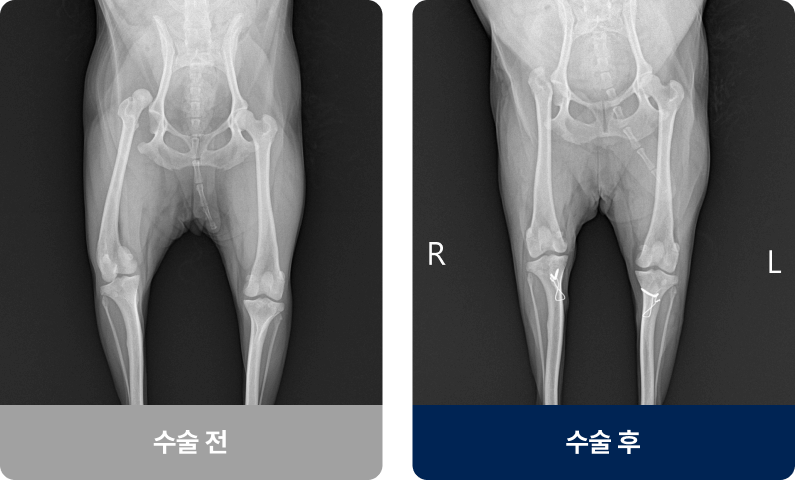

슬개골(무릎뼈)이 대퇴골 고랑에서 안쪽(내측)으로 빠지는 상태로, 소형견에서 자주 발생하는 관절 질환입니다. 주로 선천적인 영향이 대부분이고 후천적인 요인으로는 교통사고나 외부적인 충격으로 발생하며, 일시적으로 다리를 들고 서있다가 다시 내려놓는 증상을 보입니다.